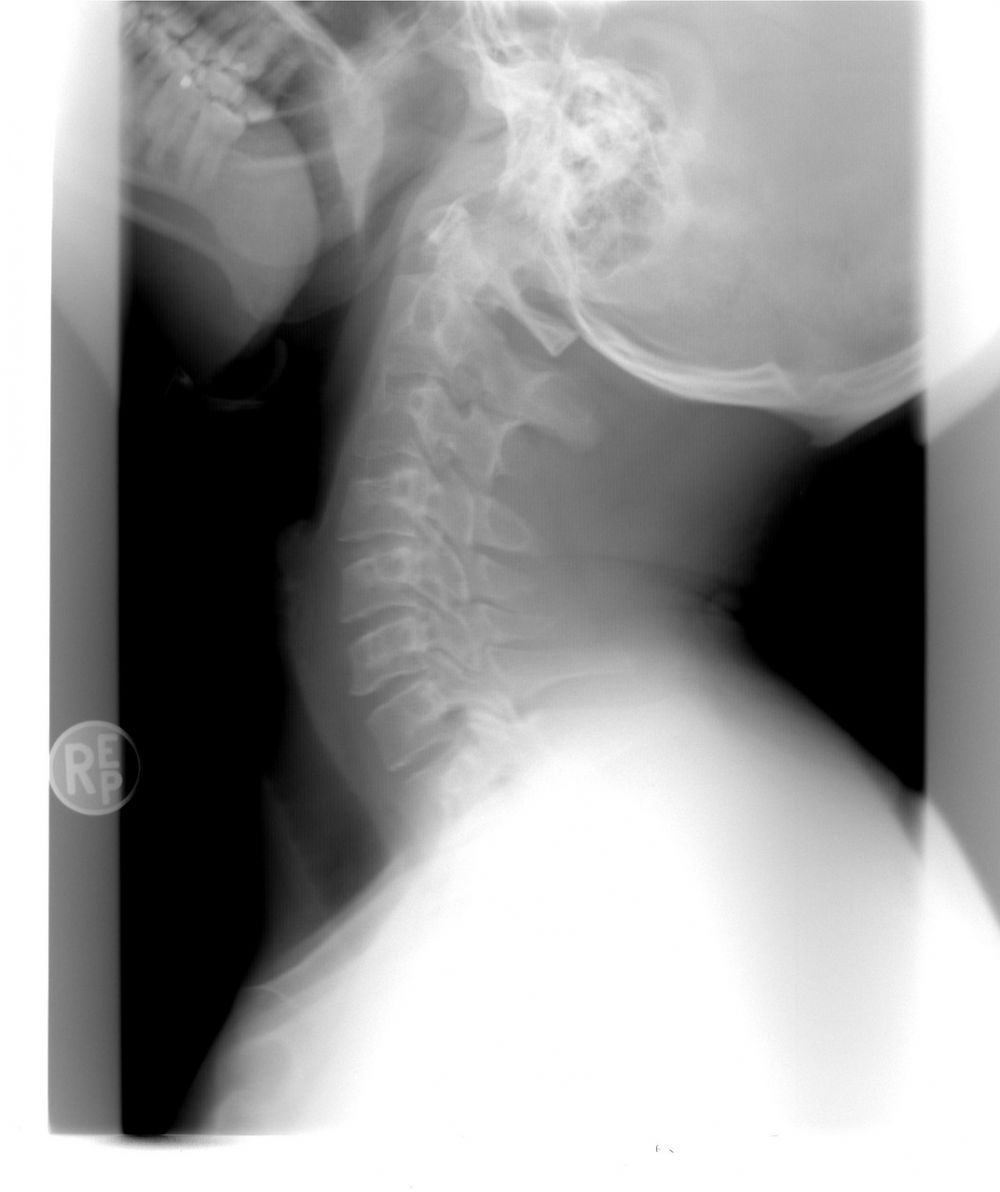

Røntgenundersøgelse

15 september 2024